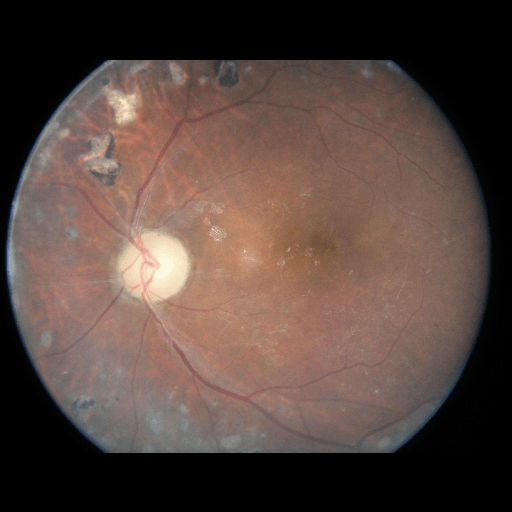

We conducted a case study on diagnosing diabetic retinopathy with ensembles of DL models. For benchmarking the performance of our ensemble-based solutions under the scheme described in Sec.3.3, we used two popular collections of diabetic retinopathy image data, the Kaggle Diabetic Retinopathy dataset [22] (hereafter referred to as “Kaggle-DR”) and the Messidor-2 dataset [23], each respectively consisting of and high resolution images. Diabetic retinopathy is graded into five SLs, as displayed in Figure 2. Following the problem setup used in previous papers [24], we trained models to distinguish the referable (SL2-4) cases from the non-referable ones (SL0 & SL1) (see Section B.1 for more detailed descriptions). We also tested our trained ensemble models on two o.o.d. image datasets (ImageNet [25] and CIFAR-10 [26]) to examine their capabilities of identifying o.o.d. inputs (see Section B in the supplementary materials).

5.1 Distribution of Uncertainty Scores

Distribution of Uncertainty Scores Across Different Severity Levels As explained in Section 3, each uncertainty metric essentially defines an order/ranking among the data points. We conducted an analysis to better understand what data will be assigned high uncertainty under a particular uncertainty metric . Picking out the highest ranked data points (), we calculated the ratio of data points from each SL. Figure 4 summarizes the results as box plots for the Kaggle-DR and the Messidor-2 datasets; additional detailed statistics can be found in Table S.1 in the supplementary materials. From the plot and table, SL1 & SL2 examples account for a higher proportion among the top-ranked uncertain examples across the three ensemble methods. This finding matches our intuition that incipient disease examples (SL1 & SL2) are more likely to be considered uncertain by ensemble methods due to their ambiguity.

The Kaggle-DR dataset comprises high resolution images. The presence of diabetic retinopathy is rated into five different SLs: no-DR (SL0), mild (SL1), moderate (SL2), severe (SL3), and proliferate (SL4), as illustrated in Figure 2. We divided the Kaggle-DR dataset into a development set and a test set, which respectively consisted of and images. The data in the development set were used to train and validate our Deep Learning (DL) models. The Messidor-2 dataset [38] that consisted of images was also used in our experiment as an additional dataset to test the true generalization performance of the models trained on the Kaggle-DR dataset. Images in Messidor-2 dataset were graded into the five SLs as in the Kaggle-DR dataset. Figure S.1 provides an illustration of the datasets used in our experiments.

The image data used in our experiment were all unified into square-shaped images with resolutions or in our preprocessing procedures. For training each neural network model, only images of the same resolution were used. The original images came with either of the two forms as exemplified in Figure S.2. In the first form (Figure 2(a)), the entire fundus was visible in the image. We cropped the image such that the fundus was tightly fitted inside the square. In the second form of input images shown in Figure 2(b), part of the fundus was not visible. We padded blank strips to make the image square-shaped and in a unified resolution. See the provided code for further details.